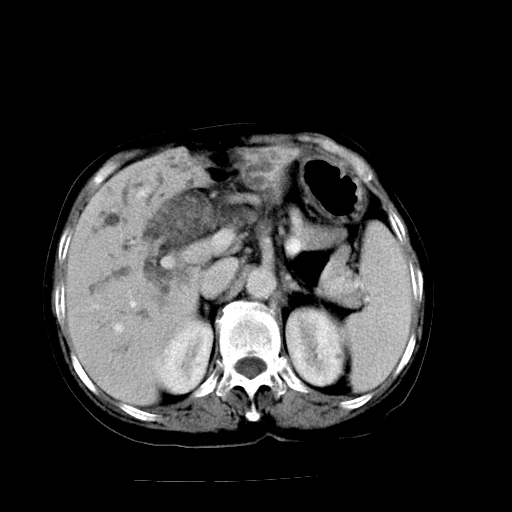

以下是引用卜一在2009-4-7 5:06:00的发言:[br]左右肝内胆管结石伴扩张合并胆系感染;不除外胆管细胞癌可能。支持! [br] [br]

以下是引用随光逐影在2009-4-7 8:21:00的发言:[br]肝内外胆管多发性结石并肝内外胆管扩张;胆系感染。